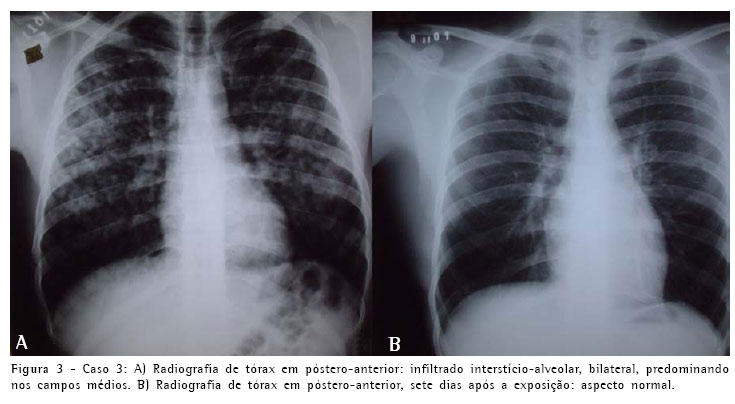

O outro paciente era um homem branco, de 19 anos, também residente em Goiânia, auxiliar de produção, que estava trabalhando junto com os outros pacientes, e que foi submetido à exposição ambiental concomitante pelo período de uma hora. Procurou atendimento de emergência no mesmo hospital, acompanhado pelo paciente primeiramente relatado. Queixava-se de dispnéia que se iniciou durante a exposição, com piora progressiva, associada a tosse seca intensa. Este paciente não referia sintomas relacionados ao sistema digestivo ou irritação de mucosa ocular ou nasal. Previamente hígido, negava tabagismo ou qualquer enfermidade importante e não fazia uso de medicação de rotina. Não tinha antecedentes de doenças familiares dignos de nota. Na admissão estava em bom estado geral, taquipnéico, cianótico +/4, com murmúrio vesicular fisiológico com estertores finos difusos. Os demais órgãos ou sistemas apresentavam-se sem alterações. A saturação periférica de oxigênio em ar ambiente era de 84%. A radiografia simples de tórax, de modo semelhante ao dos pacientes anteriores, mostrava infiltradoalveolar difuso e com áreas de confluência (Figura 3). O paciente foi hospitalizado em outro hospital da rede do Sistema Único de Saúde, por cinco dias, onde recebeu gatifloxacina na dose de 500 mg/dia, não tendo sido tratado com corticosteróides. Apresentou melhora clínica, e recebeu alta assintomático. Retornou ao Hospital das Clínicas da Universidade Federal de Goiás para acompanhamento ambulatorial oito dias após a exposição, quando realizou radiografia de tórax, espirometria, gasometria arterial e teste de difusão do monóxido de carbono, que apresentaram resultados normais.

O quadro clínico e radiológico dos três pacientes foi compatível com edema pulmonar e insuficiência respiratória aguda. A evolução revelou-se favorável e no seguimento clínico, radiológico (Figuras 1, 2 e 3) e de função pulmonar por dezoito meses não apresentaram nenhuma repercussão respiratória.